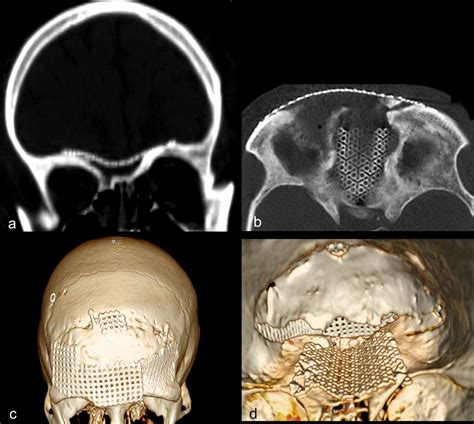

• Computed Tomography (CT): Offers high-resolution images of bony structures and is useful for planning the surgical approach.

3D Printing and Modeling

3D printing and modeling technologies are used to create detailed replicas of the skull base and surrounding structures. These models help surgeons to plan and practice complex procedures, improving surgical outcomes.